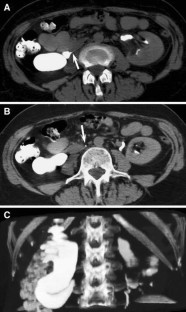

Usefulness of computed tomography performed immediately after excretory urography in patients with delayed opacification or dilated upper urinary tract of unknown cause

To evaluate the diagnostic value of computed tomography (CT) performed immediately after excretory urography (EU) in patients with delayed renal opacification or dilated upper urinary system with nonconclusive diagnosis after EU.

CT was performed immediately after EU in 39 patients with delayed opacification or dilated upper urinary system of unknown cause, without additional intravenous contrast administration for the CT study. We classified EU + CT findings as benign or malignant causes and we compared our results with the final diagnosis.

The combination of EU + CT correctly diagnosed 38 out of the 39 cases with a sensitivity of 97%. Correct diagnosis was established in all malignant cases (n = 17) but one benign case consistent with blood clots in the upper urinary tract was incorrectly diagnosed as a multicentric urothelial carcinoma. Sensitivity, specificity, and accuracy for the diagnosis of the underlying cause with EU + CT was 100%, 95%, and 97%, respectively. The final diagnoses were: urothelial carcinoma (n = 10), stone disease (n = 10), bladder tumor (n = 4), benign post-treatment ureteral stenosis (n = 4), ureteral invasion (n = 3), benign bladder disease (n = 2), urinary tract infections (n = 2), crossing vessels (n = 1), ureteropelvic junction obstruction (n = 1), retrocaval ureter (n = 1), and blood clots in the upper urinary tract due to bleeding renal metastasis from lung cancer (n = 1).

Combined EU and CT study allowed correct diagnosis of the underlying cause of delayed excretion or upper urinary tract dilatation in 97% of cases. The combination of EU and CT provides diagnosis reducing time and radiation.